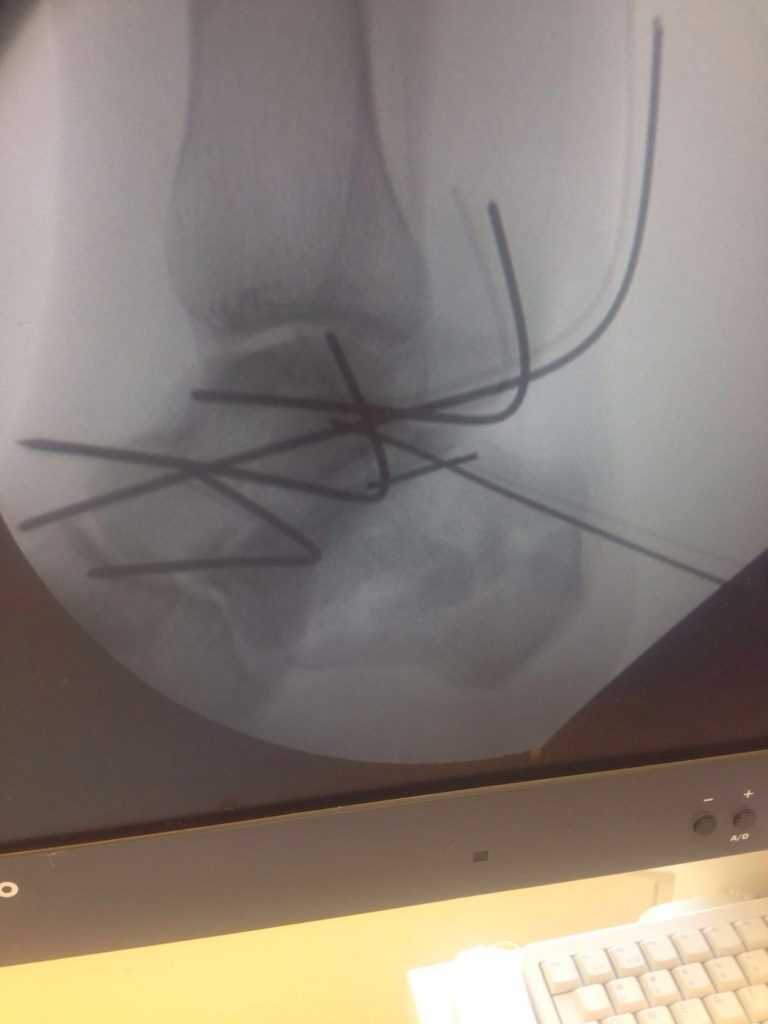

Операция – открытая репозиция, остеосинтез пяточной кости пластиной с костной ксенопластикой материалом «Остеоматрикс». На контрольных снимках в три месяца имеется консолидация перелома, миграции фиксатора нет, имеется остеоинтеграция ксенопластического материала.